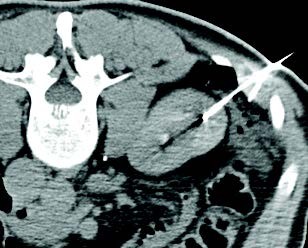

Un hombre de 66 años presentó un CCR endofítico de 2.0 cm x 2.1 cm en el lado izquierdo, y la biopsia confirmó carcinoma de células renales claras. Las imágenes CR iniciales el día del procedimiento demostraron la lesión y el colon adyacente, que probablemente se lesionaría si no se moviera. Se realizó crioablación con tres agujas IceRod™ 1.5 CX para el tratamiento y se utilizó una aguja yueh para introducir solución salina normal y realizar hidrodisección del colon adyacente. El paciente no tuvo dolor ni quejas significativas; fue dado de alta y regresó al trabajo el mismo día del procedimiento. Continúa sin evidencia de enfermedad residual/recurrencia un año después.

Shamar Young, MD | Universidad de Minnesota | Minneapolis, MN